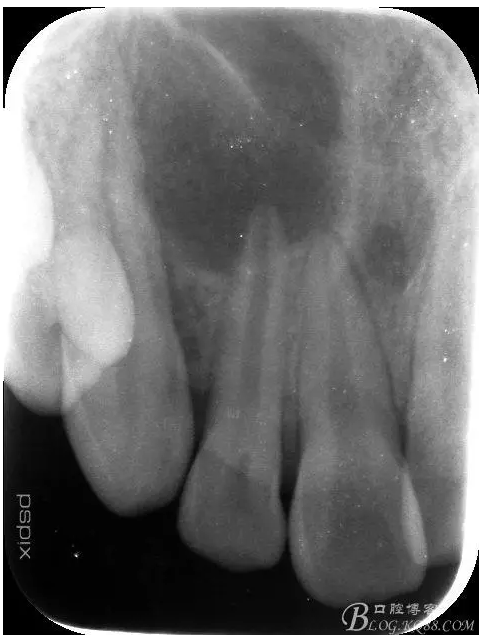

患者、宋xx,男、16歲。主訴:右側(cè)面部腫脹三天。并自覺(jué)鼻腔溢膿。??茩z查:患者右側(cè)眶下區(qū)腫脹隆起,皮膚未變紅,觸痛不明顯,鼻腔檢查未見(jiàn)瘺口。也無(wú)滲出物流出??趦?nèi)檢查:12牙冠未變色。舌側(cè)有一畸形溝,唇側(cè)前庭溝粘膜紅腫隆起,未見(jiàn) 有瘺道觸診有乒乓感,x線檢查:12根尖孔未徹底發(fā)育完成,根尖有橢圓形陰影,大小如花生米,邊界清楚。診斷:12根尖囊腫。處理建議:建議 1.抗感染治療,控制感染的根尖囊腫。2.感染消退后行12根管治療+手術(shù)摘除囊腫+根管倒充填?;颊咄庵委煼桨福炇中g(shù)知情同意書(shū)。

1.術(shù)前的根尖片檢查及根管治療影像: